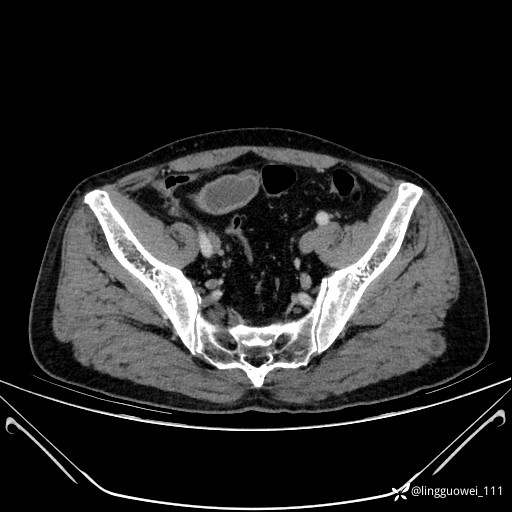

62岁,男,2天前无明显诱因出现下腹部疼痛不适,呈持续性,程度稍剧,同时伴有尿频、尿急及尿不尽感,无畏寒、发热。

平扫: